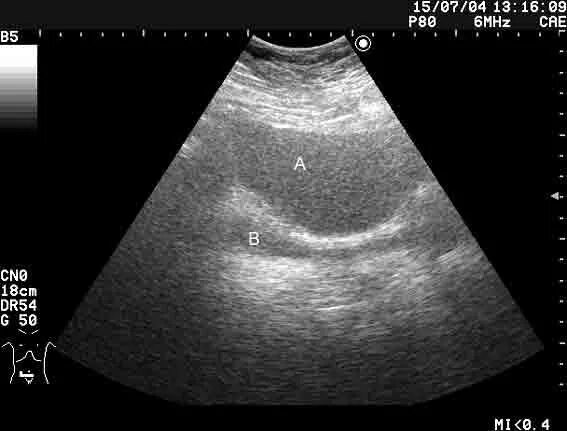

Асцит в малом тазу